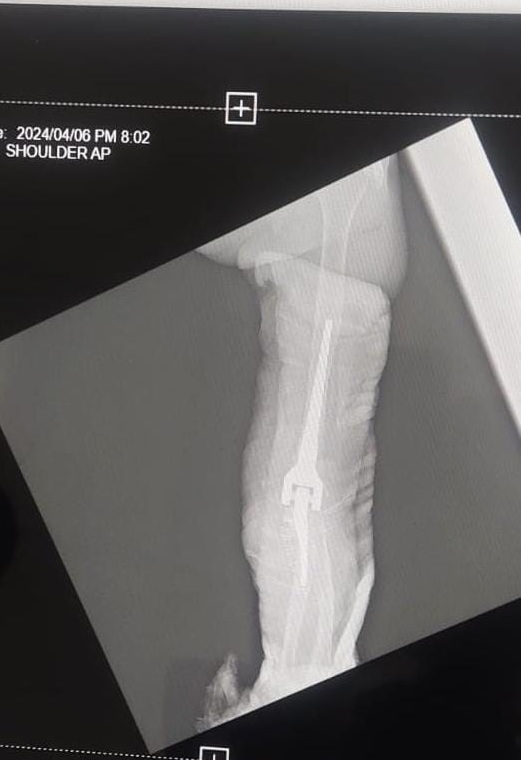

Under general and regional anesthesia, a posterior midline incision was used. A triceps-sparing approach provided access to the joint [6]. Dense fibrous tissue and synovitis were debrided. The ulnar nerve was isolated and protected. Intraoperatively, the condyles were found intact but with compromised cortical support. Instead of resection, both condyles were preserved and secured with multiple tensioned loops of no. 5 Ethibond suture, restoring the supracondylar architecture and facilitating prosthesis fit. The medullary canals were broached, and an uncemented, hinged prosthesis was implanted. Trialling confirmed joint stability and good arc of motion (0–110°). The triceps was repaired with heavy non-absorbable sutures. (Fig. 2 and 3) (Table 1).

Figure 2: Implantation of prosthesis.